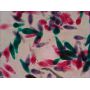

| Микроскоп бинокулярный Levenhuk 2ST - ОписаниеМикроскоп Levenhuk 2ST – современный инструментальный микроскоп с большим рабочим расстоянием в 60 мм и увеличением 40х. Такое рабочее расстояние позволяет проводить исследование не только плоских микропрепаратов и тонких срезов, но и довольно крупных образцов – кусочков горных пород, ювелирных изделий, крупных монет и т.д.

Оптические элементы изготовлены из специального стекла высокой прозрачности, что позволяет передавать качественное реалистичное изображение наблюдаемых объектов. Для регулировки резкости предусмотрена возможность грубой фокусировки – на корпусе микроскопа есть специальное колесико. При проведении исследований используется естественное освещение, поэтому вам не придется тратить средства на покупку батареек или аккумуляторов.